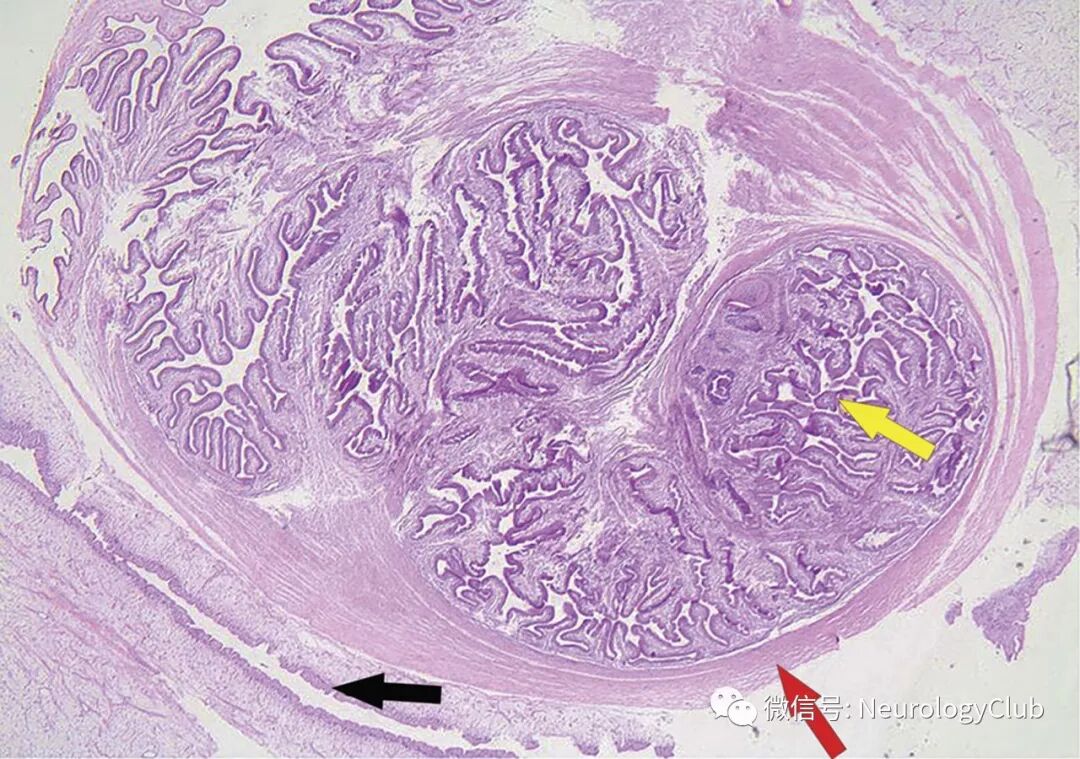

(图2:组织病理学可见包在荚膜内的囊尾蚴幼虫[H&E,40×];外膜[黑箭],幼虫头节[红箭]和幼虫肠道[黄箭])

患者接受显微手术完全切除病灶。解剖病理报告(图2)证实为囊虫病。